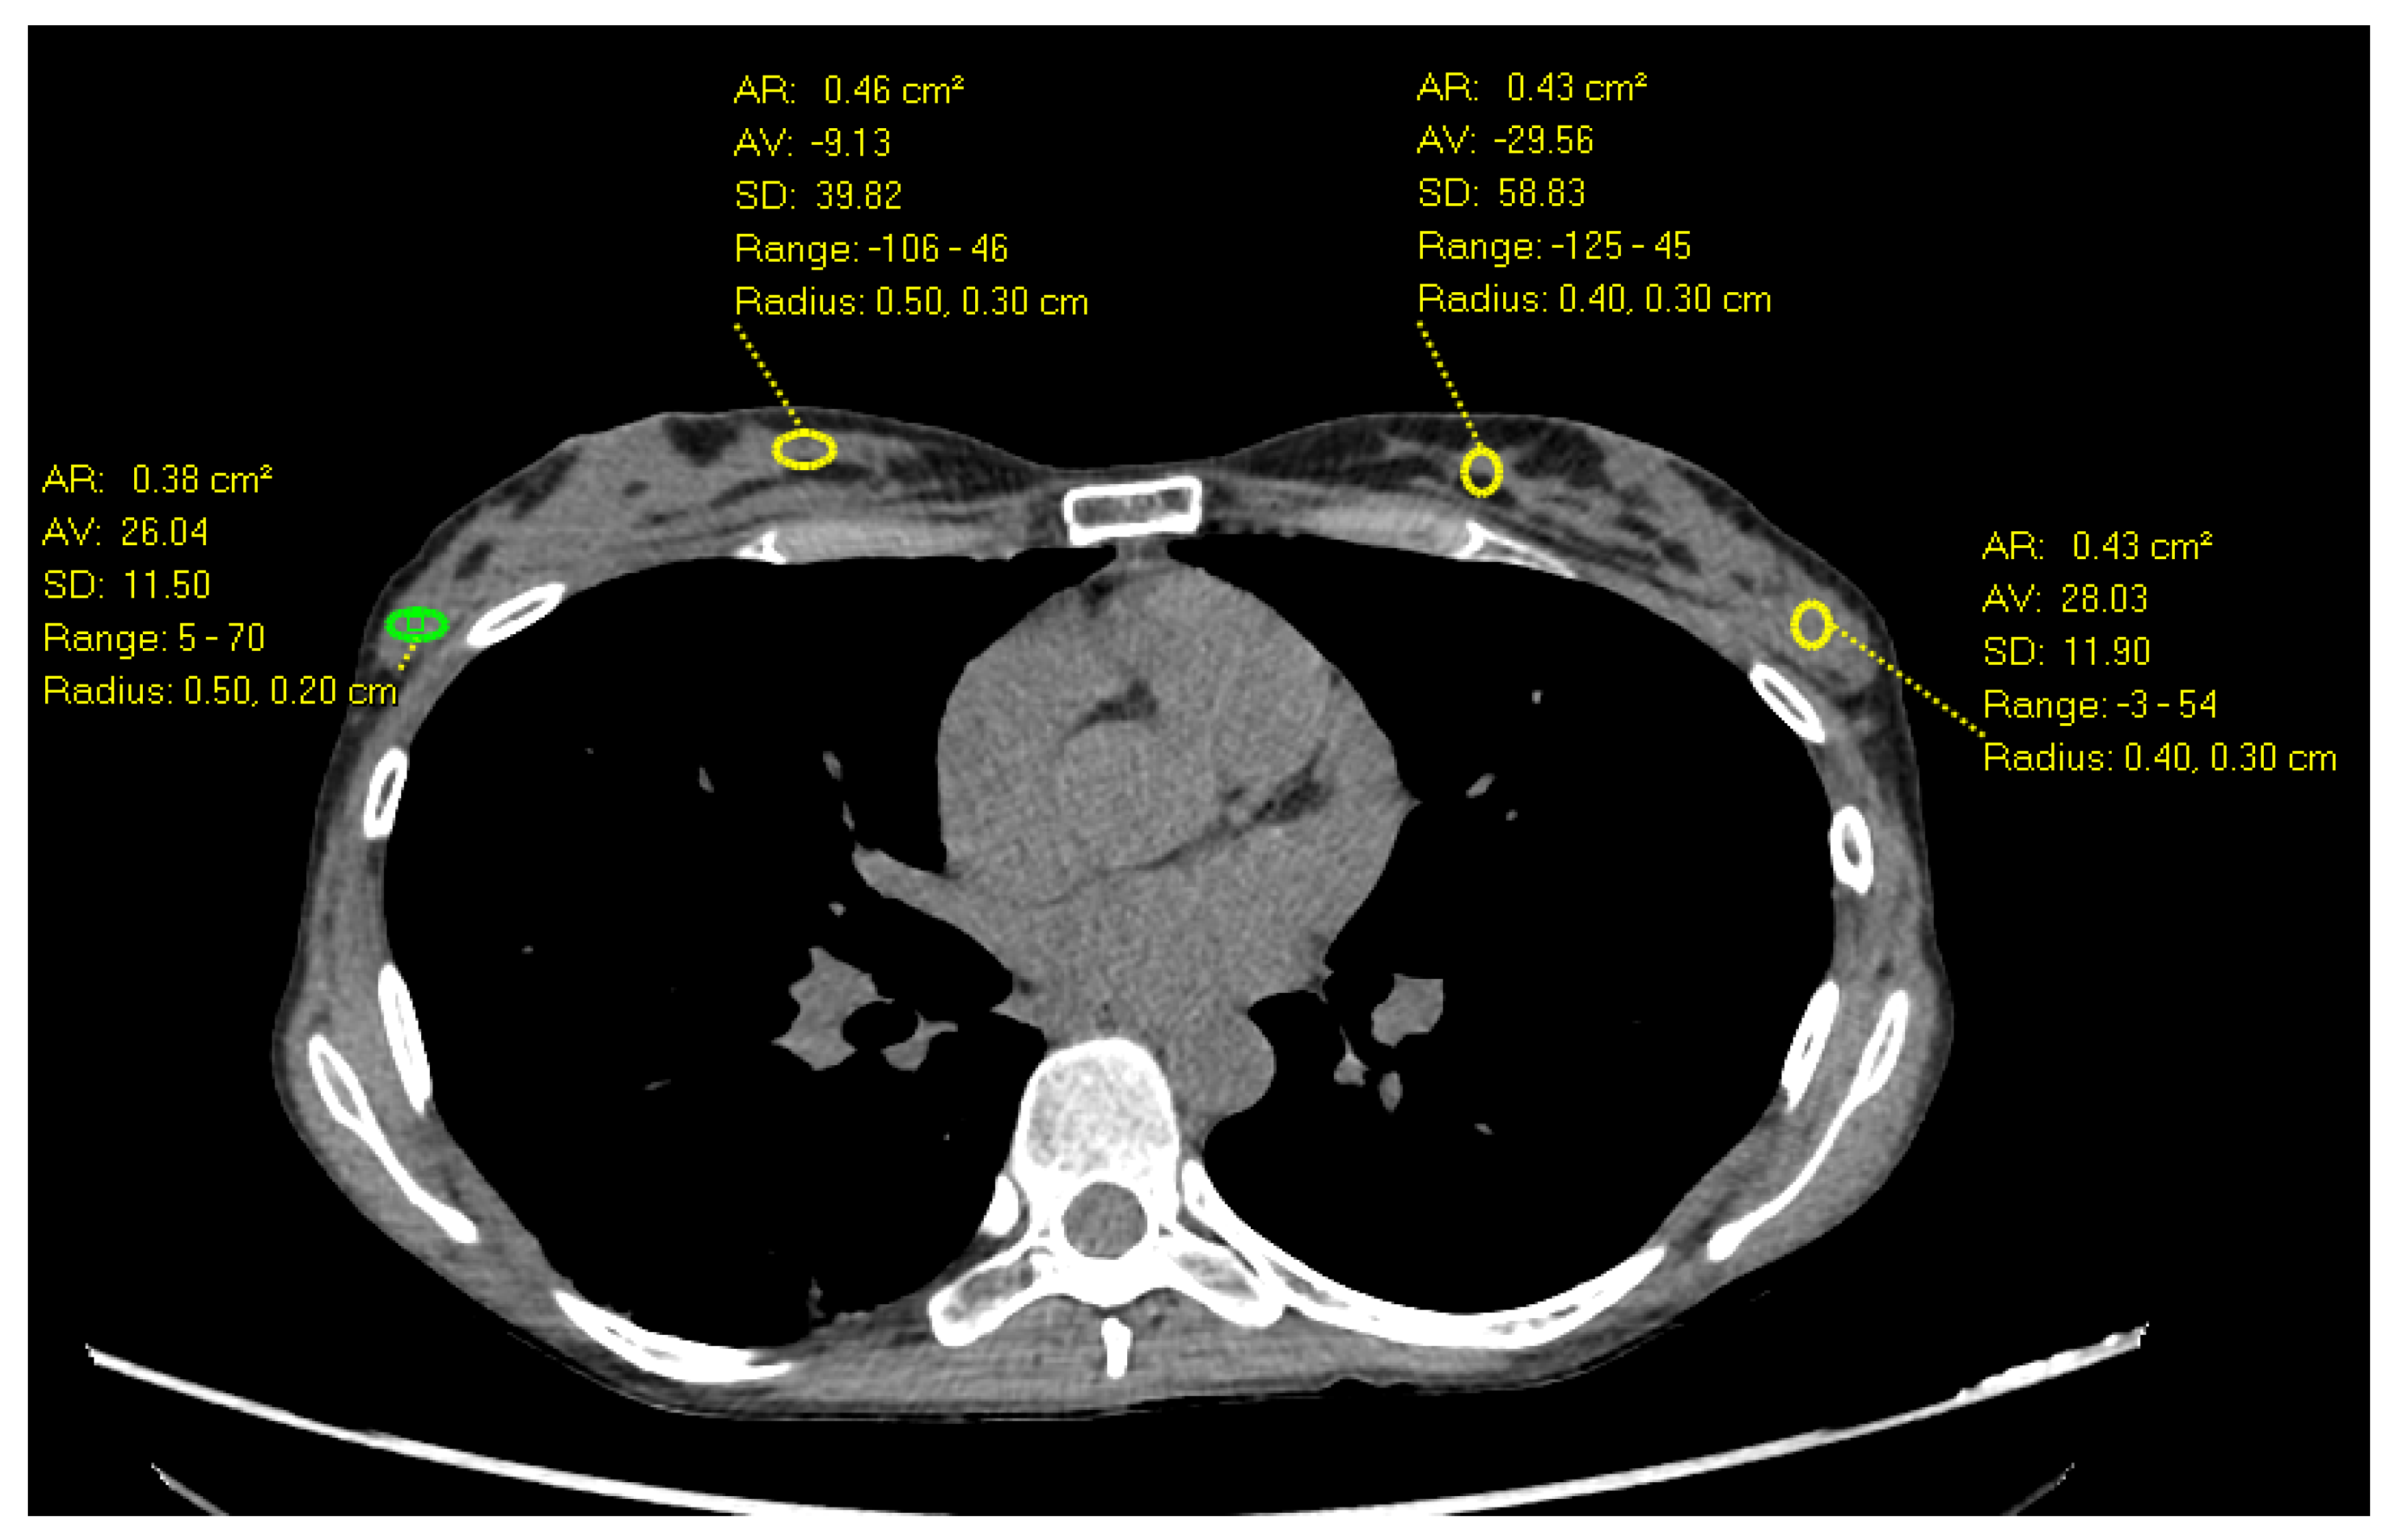

Breast Cancer Treatment (PDQ®) - American Association for。nejmcpc2309499_f1.jpg。Frontiers | (KAUH-BCMD) dataset: advancing mammographic。乳がんに関する最新の情報を提供するモノグラフ。Breast cancer: Know the facts | CNN。病理学や治療法についての詳細な章を含む。。- タイトル: Breast Cancer- 編集者: B. Hoogstraten, I. Burn, H.J. G. Bloom- 出版社: Springer-Verlag- 内容: 乳がんに関する最新の情報を提供するモノグラフ- 特徴: 病理学、診断、治療法についての詳細な章を含む- シリーズ名: UICCご覧いただきありがとうございます。視能検査学。